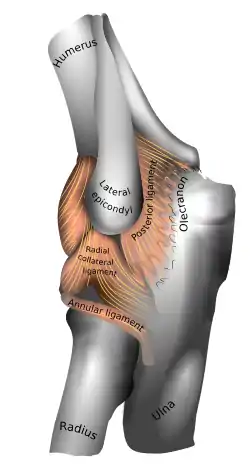

Ligaments

Left elbow-joint

Left: anterior and ulnar collateral ligaments

Right: posterior and radial collateral ligaments

The elbow, like other joints, has ligaments on either side. These are triangular bands which blend with the joint capsule. They are positioned so that they always lie across the transverse joint axis and are, therefore, always relatively tense and impose strict limitations on abduction, adduction, and axial rotation at the elbow.[8]

The ulnar collateral ligament has its apex on the medial epicondyle. Its anterior band stretches from the anterior side of the medial epicondyle to the medial edge of the coronoid process, while the posterior band stretches from posterior side of the medial epicondyle to the medial side of the olecranon. These two bands are separated by a thinner intermediate part and their distal attachments are united by a transverse band below which the synovial membrane protrudes during joint movements. The anterior band is closely associated with the tendon of the superficial flexor muscles of the forearm, even being the origin of flexor digitorum superficialis. The ulnar nerve crosses the intermediate part as it enters the forearm.[8]

The radial collateral ligament is attached to the lateral epicondyle below the common extensor tendon. Less distinct than the ulnar collateral ligament, this ligament blends with the annular ligament of the radius and its margins are attached near the radial notch of the ulna.[8]